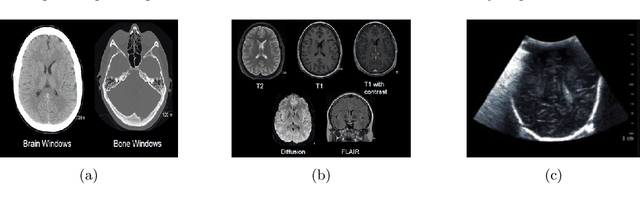

The application of machine learning to radiological images is an increasingly active research area that is expected to grow in the next five to ten years. Recent advances in machine learning have the potential to recognize and classify complex patterns from different radiological imaging modalities such as x-rays, computed tomography, magnetic resonance imaging and positron emission tomography imaging. In many applications, machine learning based systems have shown comparable performance to human decision-making. The applications of machine learning are the key ingredients of future clinical decision making and monitoring systems. This review covers the fundamental concepts behind various machine learning techniques and their applications in several radiological imaging areas, such as medical image segmentation, brain function studies and neurological disease diagnosis, as well as computer-aided systems, image registration, and content-based image retrieval systems. Synchronistically, we will briefly discuss current challenges and future directions regarding the application of machine learning in radiological imaging. By giving insight on how take advantage of machine learning powered applications, we expect that clinicians can prevent and diagnose diseases more accurately and efficiently.